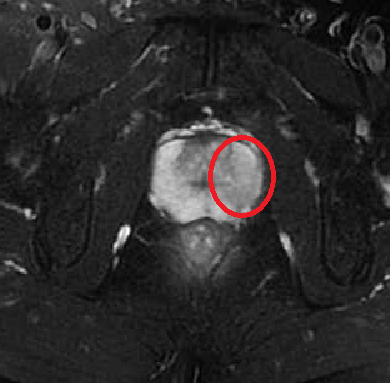

陈大伯,中等身材,早在十多年前,就出现了尿频、尿急、小便不畅等症状,但一家人都误以为与年纪有关,加上老人不喜欢上医院,大家就都没放心上。直到他来到医院体检,查出血清TPSA高达12.16(见图2),前列腺B超、磁共振均提示前列腺癌考虑。

(陈大伯的磁共振影像,术后病理证实为前列腺癌)

好在,陈大伯发现的还算及时,属于临床局限型前列腺癌。目前,陈大伯一切恢复良好,术后复查PSA,结果都在参考范围内。